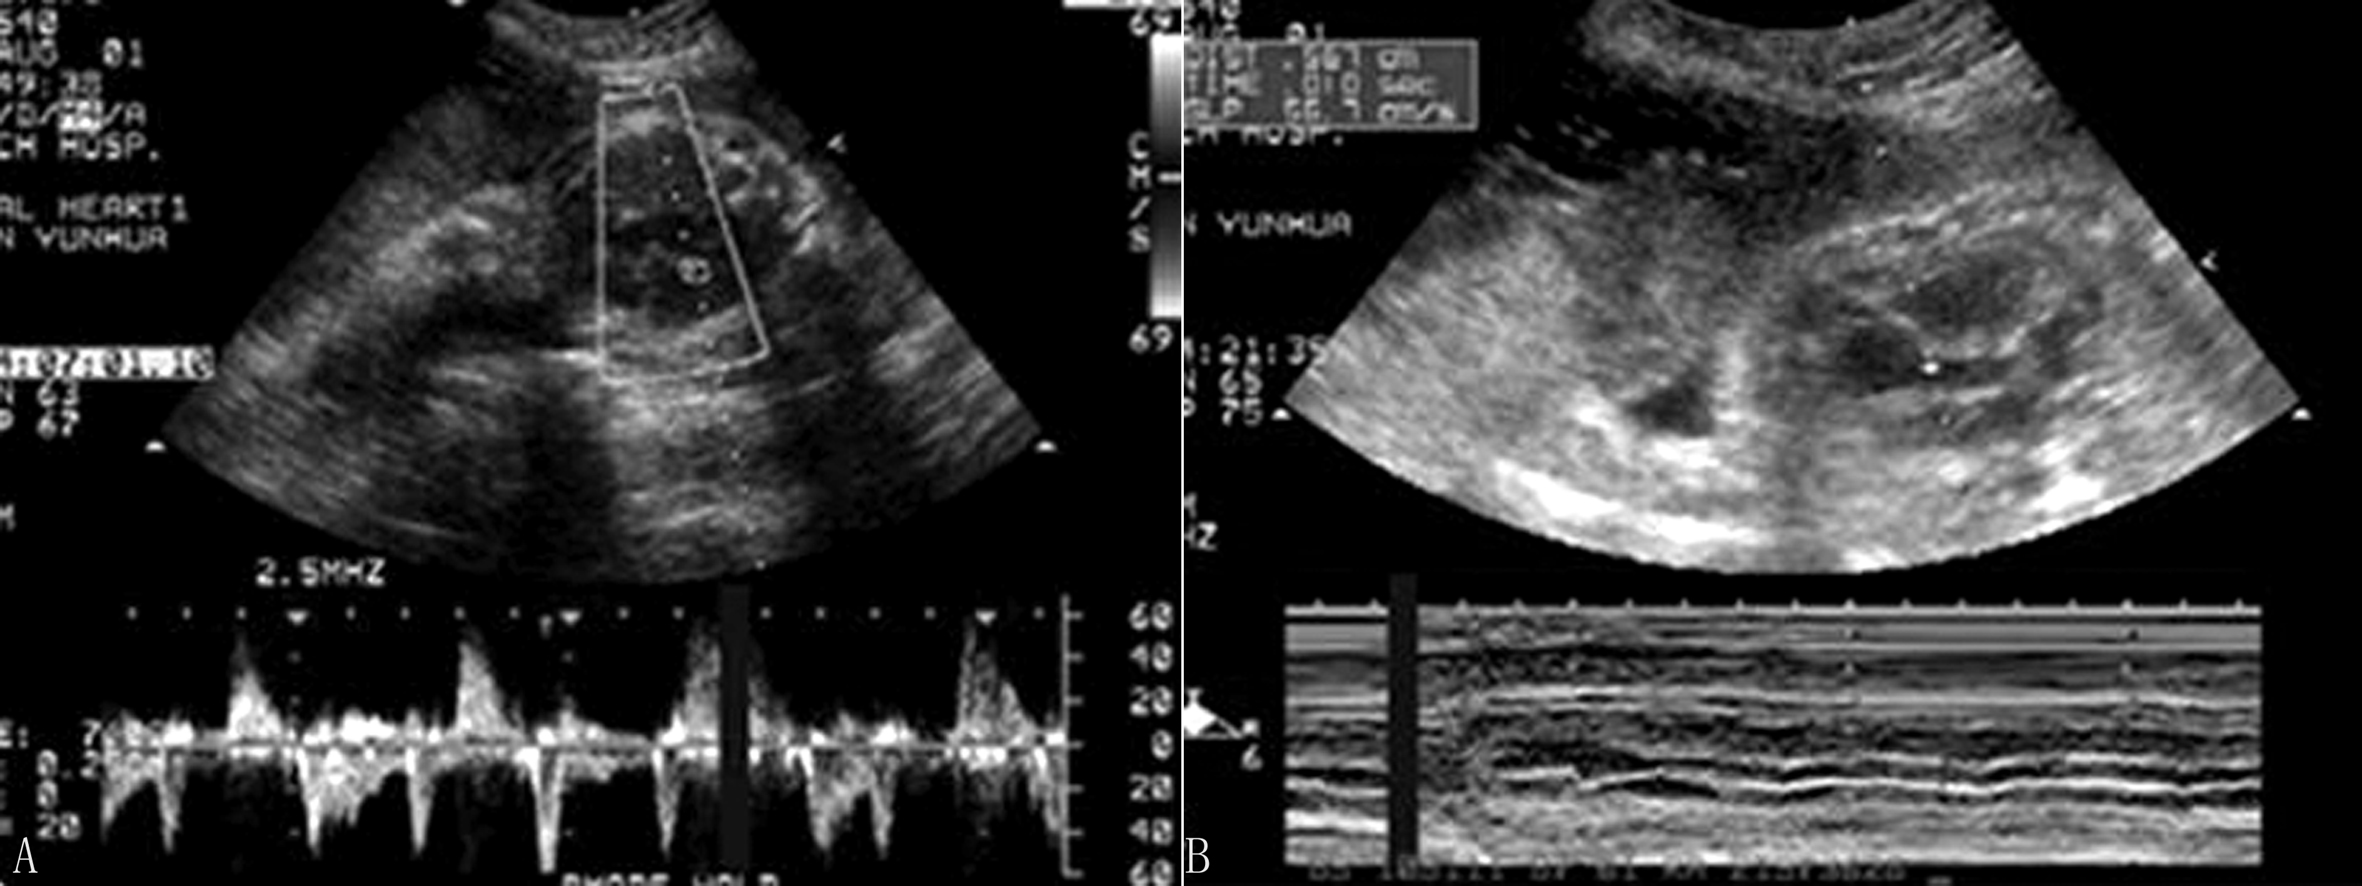

2.超声诊断要点 完全性房室传导阻滞心房收缩波与心室收缩波无关联,各有自己的节律。不完全性房室传导阻滞在多普勒血流时间流速曲线图上表现为:心室收缩波不是紧跟在心房收缩波后面,但与心房收缩波有关,如心室收缩波紧跟在心房收缩波后面应考虑心动过缓可能。M型超声由于振幅较低,有时难以判断,现多用脉冲多普勒时间流速曲线图进行分析,根据心房收缩波与心室收缩波的关系,得出推断结论(图4)。

图4 胎儿完全性房室传导阻滞

2.超声诊断要点 交界性早搏难以由超声心动图诊断,房性早搏和室性早搏可通过M型超声振幅或脉冲多普勒血流时间流速曲线分析间接诊断。房性早搏是心房收缩波提前出现,后面可跟随或不跟随心室收缩波,无代偿间期(图5),室性早搏是心室收缩提前出现,有代偿间期可作为鉴别点(图6)。

图5 胎儿频发房性早搏:细箭头处为正常的心房收缩波,粗箭头处为提前搏动的心房收缩波

图6 胎儿室性早搏: 箭头处为提前搏动的室性早搏,其后有一较长的代偿间期